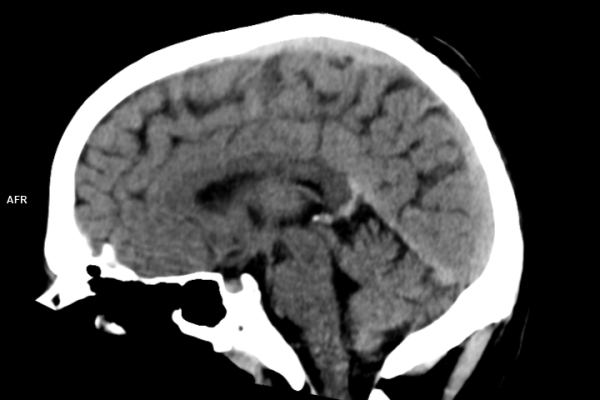

CT Untersuchung Bild

Die MRT (Magnetresonanztomographie) arbeitet mit Magnetfeldern und Radiowellen und eignet sich besonders für Untersuchungen der Weichteile wie Gehirn, Muskeln oder Gelenke. Die CT (Computertomographie) nutzt Röntgenstrahlen und liefert schnelle, hochauflösende Bilder, insbesondere für Knochen, Lunge oder innere Organe. Die Wahl der jeweiligen Untersuchung richtet sich an das individuelle Krankheitsbild und wird bei der Überweisung festgelegt.